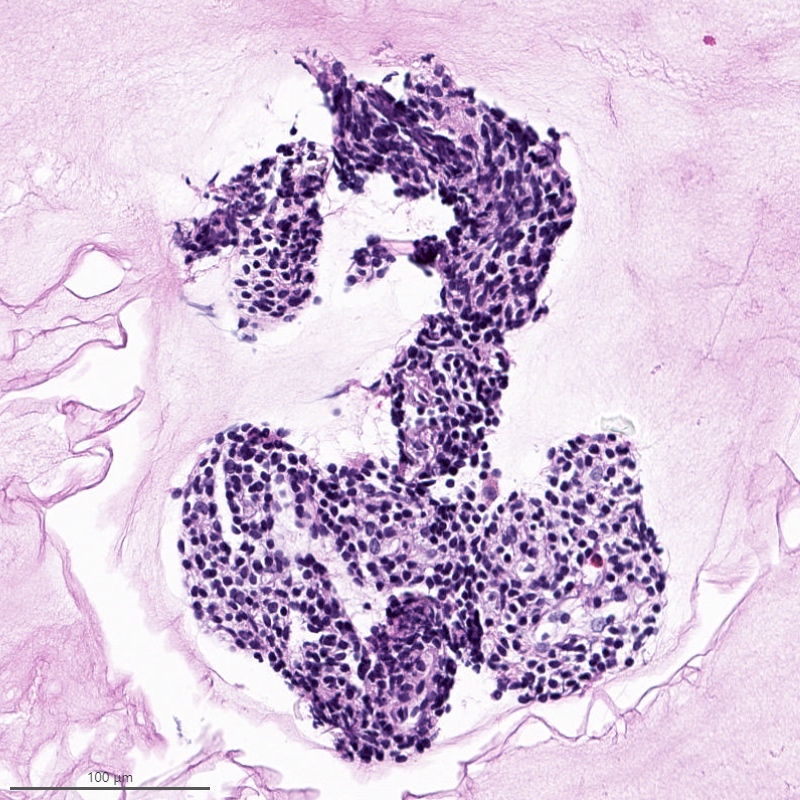

Microscopic (histologic) description

- Irregular cellular islands, forming permeative tongue-like pattern of myometrial invasion with frequent vascular invasion

- Monotonous oval to spindle cells with minimal cytologic atypia, vesicular chromatin and scant cytoplasm

- Mitotic count is usually low (< 5/10 high power fields), necrosis is usually absent

- Tumor cells may whorl around delicate arteriolar type vessels, reminiscent of proliferative phase endometrial stroma

- May have admixed collagen bands / plaques and foamy histiocytes

- May have smooth muscle differentiation, particularly in a starburst morphology, with collagen bands radiating towards the periphery of the nodule

- Other reported types of differentiation: fibromyxoid / fibrous, sex cord-like, epithelioid, rhabdoid, endometrioid glands, pseudopapillae, clear cells, bizarre cells, adipose tissue (Mod Pathol 2016;29:S92)

Microscopic (histologic) images

Contributed by Elizabeth Kertowidjojo, M.D., Ph.D., M.P.H. and Ayse Ayhan, M.D., Ph.D.